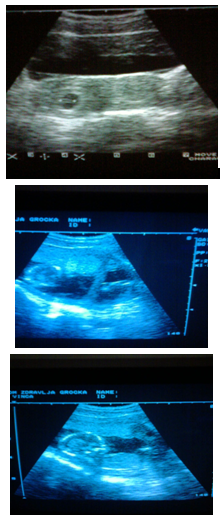

Figure 1 Patient D.M.1983.age1th pregnancy blighted ovum m.l.II.In next pregnancy ultrasound examinations were carried out 5time.A live female child was obtained by surgery1800/40.